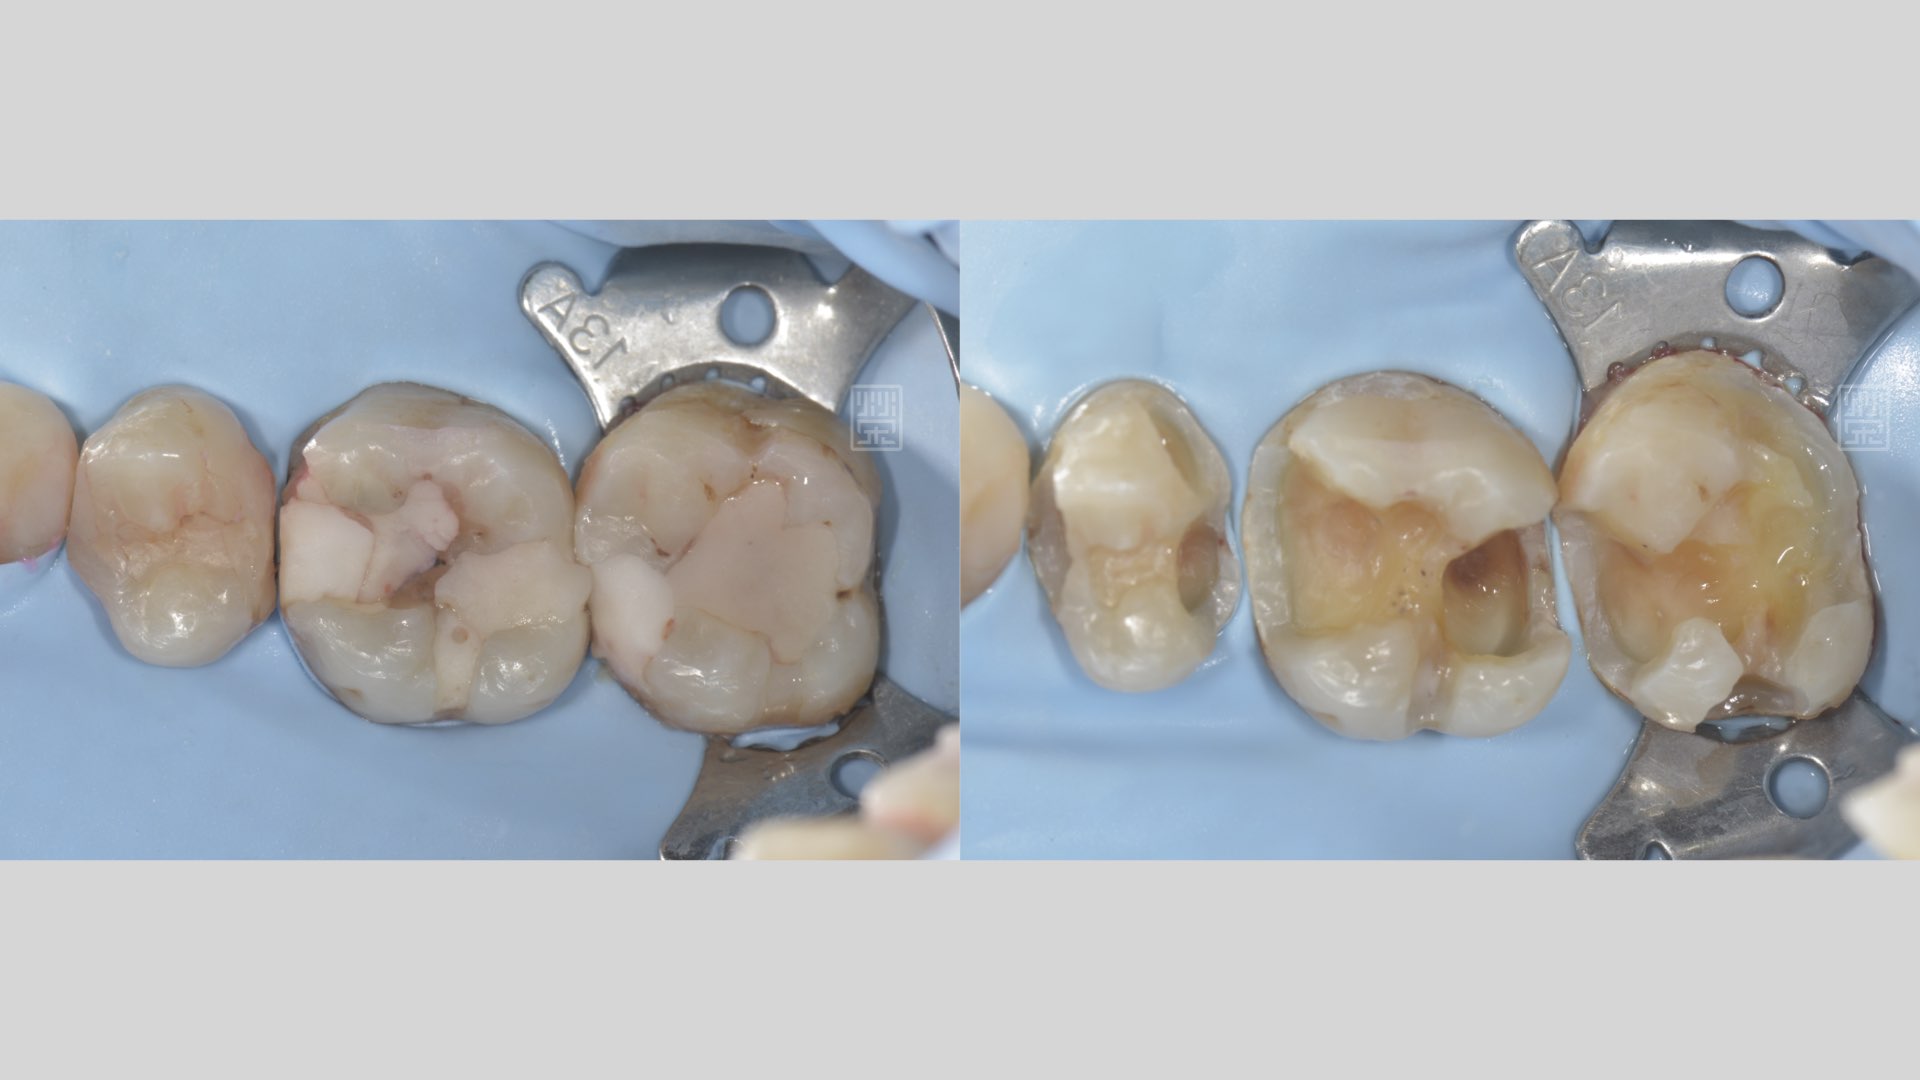

後牙蛀牙清除

後牙蛀牙清除後,牙髓受感染,MTA覆髓治療